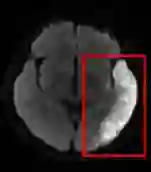

Stroke is a common disabling neurological condition that affects about one-quarter of the adult population over age 25; more than half of patients still have poor outcomes, such as permanent functional dependence or even death, after the onset of acute stroke. The aim of this study is to investigate the efficacy of diffusion-weighted MRI modalities combining with structured health profile on predicting the functional outcome to facilitate early intervention. A deep fusion learning network is proposed with two-stage training: the first stage focuses on cross-modality representation learning and the second stage on classification. Supervised contrastive learning is exploited to learn discriminative features that separate the two classes of patients from embeddings of individual modalities and from the fused multimodal embedding. The network takes as the input DWI and ADC images, and structured health profile data. The outcome is the prediction of the patient needing long-term care at 3 months after the onset of stroke. Trained and evaluated with a dataset of 3297 patients, our proposed fusion model achieves 0.87, 0.80 and 80.45% for AUC, F1-score and accuracy, respectively, outperforming existing models that consolidate both imaging and structured data in the medical domain. If trained with comprehensive clinical variables, including NIHSS and comorbidities, the gain from images on making accurate prediction is not considered substantial, but significant. However, diffusion-weighted MRI can replace NIHSS to achieve comparable level of accuracy combining with other readily available clinical variables for better generalization.